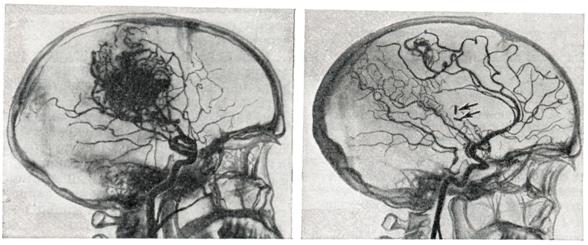

Снимки и иллюстрации микроаневризм сосудов головного мозга